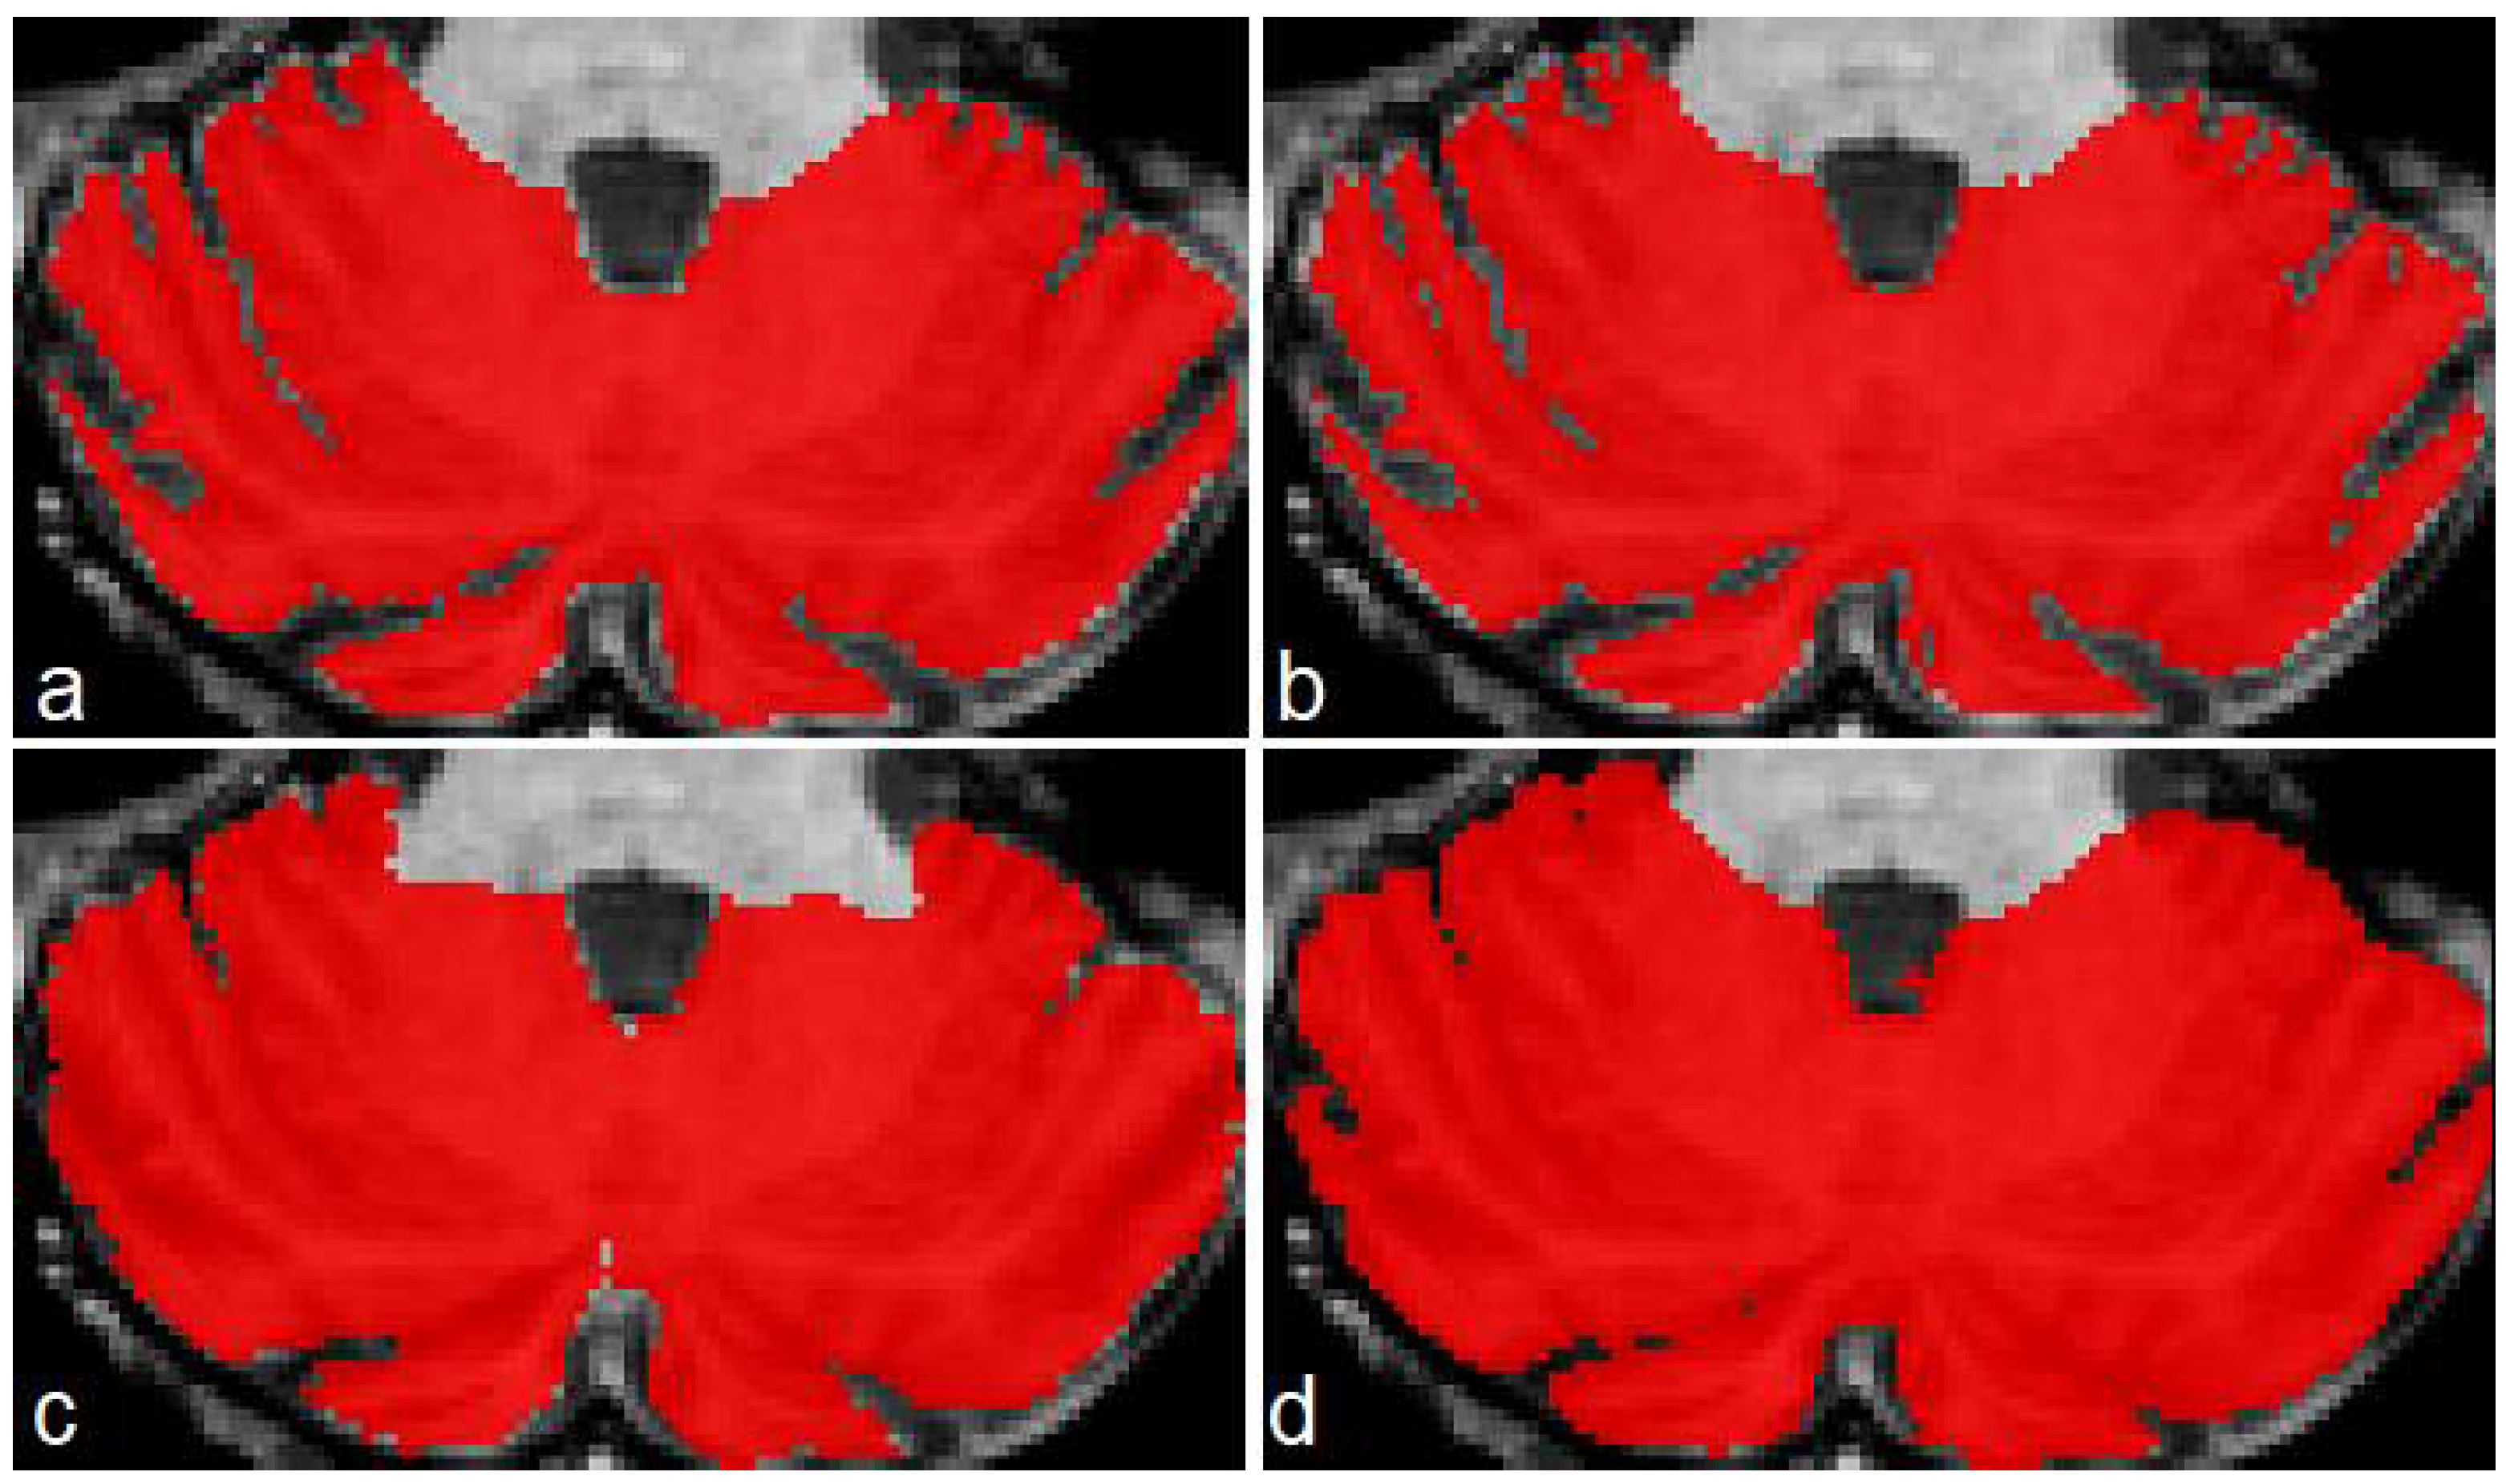

Figure 6 shows a case of the segmentations produced for this second dataset. As in the previous example, the best segmentations were produced by model M2 (Figure 6b). There are some irregularities on borders, which we think can be corrected by applying some postprocessing technique (rather than longest connected component, which is the only postprocessing we currently apply on segmentations). In this example, ACAPULCO was capable of segmenting some fissures better than CERES (Figure 6c,d).

Figure 6.

Segmentations produced by the three approaches for a sample image from the DLBS dataset. Original mask (a), followed by segmentation produced by M2 (b), CERES (c) and ACAPULCO (d).

Table 10 shows the DSC comparison for the DLBS subset. The three approaches obtained close dice scores, with a mean value of 0.967, 0.931 and 0.945, respectively. The 10 images for this comparison belong to healthy controls, which means less fissures, so the scores for ACAPULCO and CERES were increased.

Table 11 shows a comparison for the OC scores achieved in the DLBS dataset. Higher values were obtained by ACAPULCO, followed by CERES, and finally M2. The mean values were 0.998, 0.980 and 0.975, respectively. This represents the same phenomena as Table 8: segmentations produced by ACAPULCO and CERES include the original masks because of the problems when recognizing cerebellar fissures, resulting in elevated OC.

In Table 12 are included the SP scores achieved in the DLBS dataset. As in Table 9, model M2 presented the best behavior, which means that the classification of background voxels was better. Mean scores were 0.993, 0.970 and 0.977, respectively.

Results for this dataset were similar to those obtained in our five test MRIs. The model M2 presented higher DSC and SP, and lower OC than ACAPULCO and CERES. This means that M2 identifies cerebellar fissures better than the other approaches.